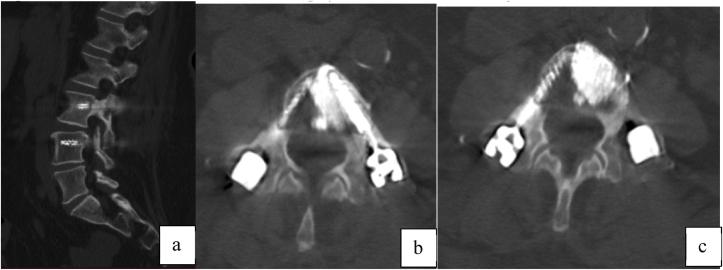

非典型腰椎椎弓根骨折。病例报告及文献比较综述:与双膦酸盐有关?可能符合股骨非典型骨折的诊断标准。

Atypical lumbar pedicle fractures. A case report and comparative review of the literature: Bisphosphonate-related? Possible matching with diagnostic criteria of atypical fractures of the femur.

In this paper we present a case of an atraumatic bilateral pedicle lumbar fracture, assuming the hypothesis of an insufficiency atypical fracture due to prolonged Alendronate therapy for osteoporosis. We highlight the various aspects for diagnosis, treatment and a review of the existing literature was carried out.

材料与方法

在本文中,我们报告了一例无创伤性双侧椎弓根腰椎骨折病例,假定其为因长期使用阿仑膦酸钠治疗骨质疏松而导致的非典型不全骨折。我们强调了诊断、治疗的各个方面,并对现有文献进行了综述。

文献中很少报道脊柱非典型骨折。椎弓根的解剖结构部分类似于长骨,被描述为后弓与椎体之间由皮质骨和松质骨核心组成的坚固桥梁。应力性骨折可由潜在的骨疾病、创伤、手术后以及应力引起。我们认为,针对非典型股骨骨折所描述的标准也是将这些罕见的椎弓根病变归类为不全性、与双膦酸盐相关骨折的有用工具。